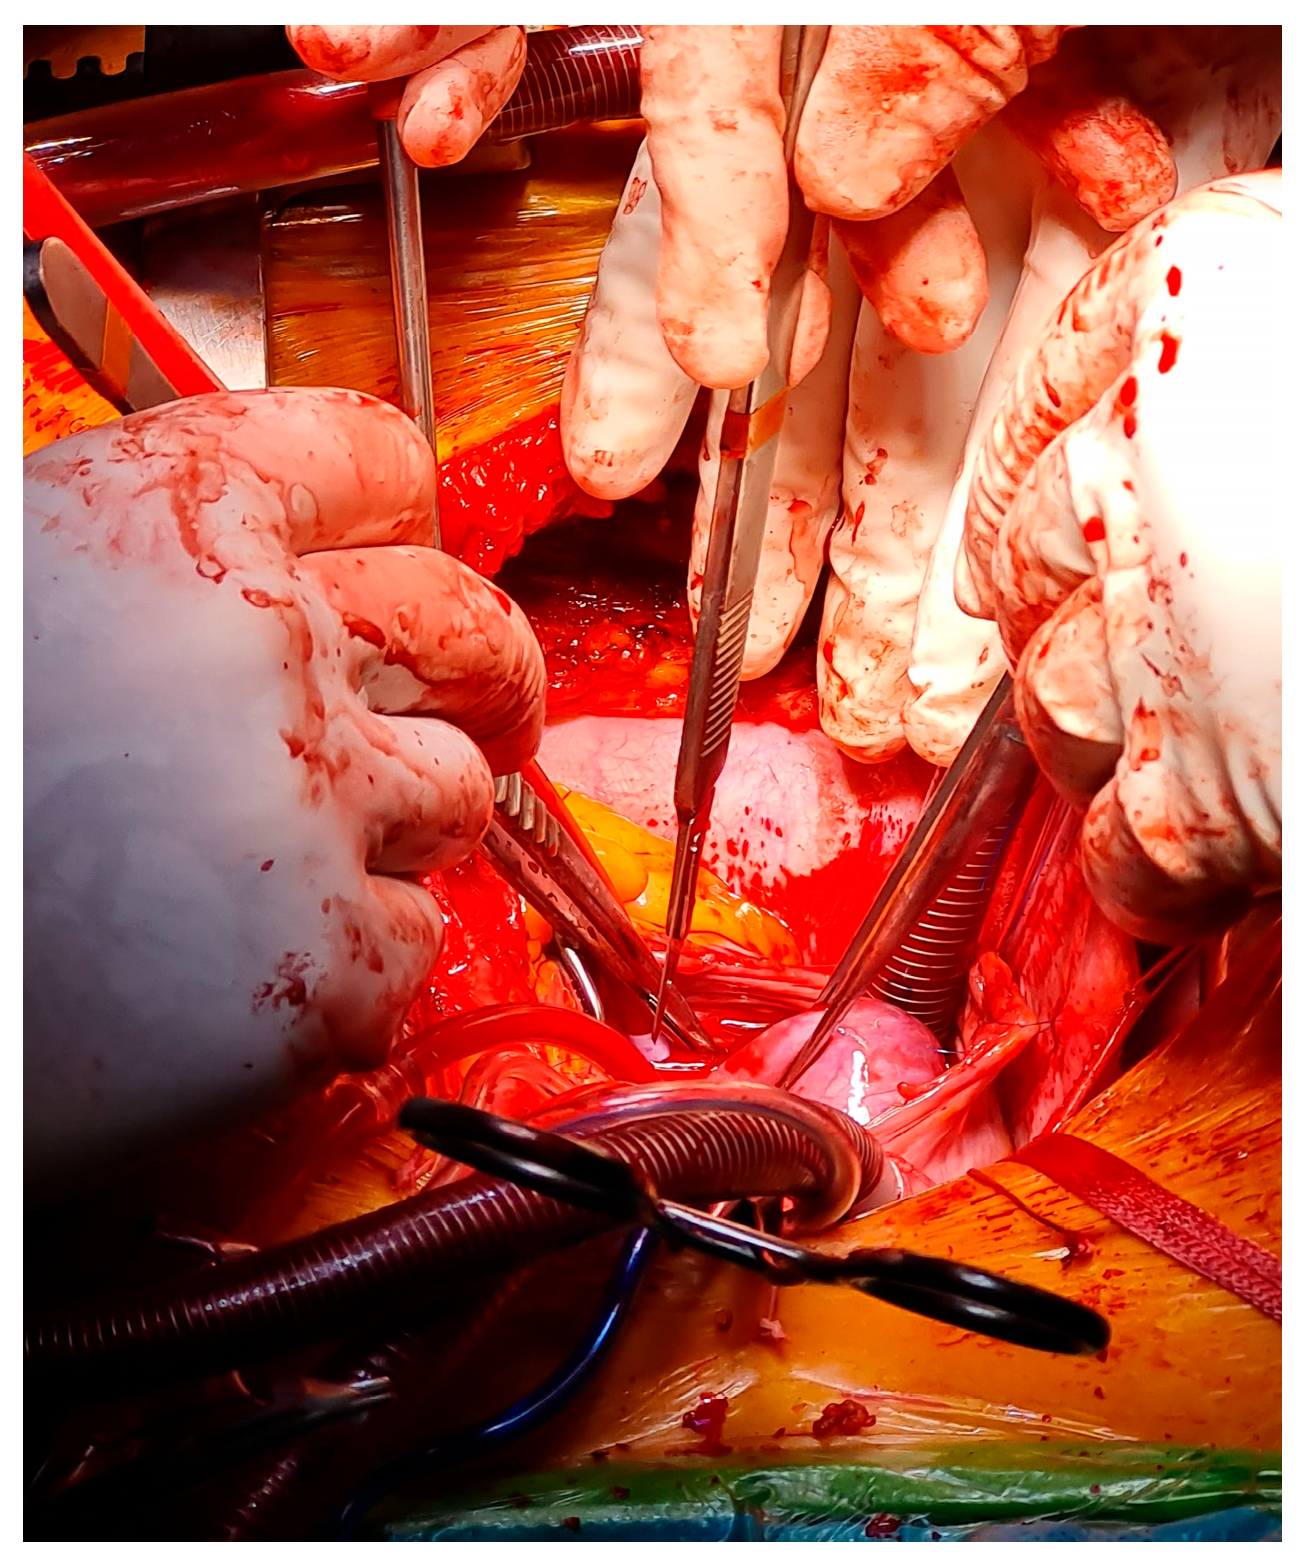

| Surgery (same admission) | Median sternotomy with cardiopulmonary bypass; en bloc excision of the right atrial mass and affected septal tissue; pericardial patch repair of atrial septal defect. |